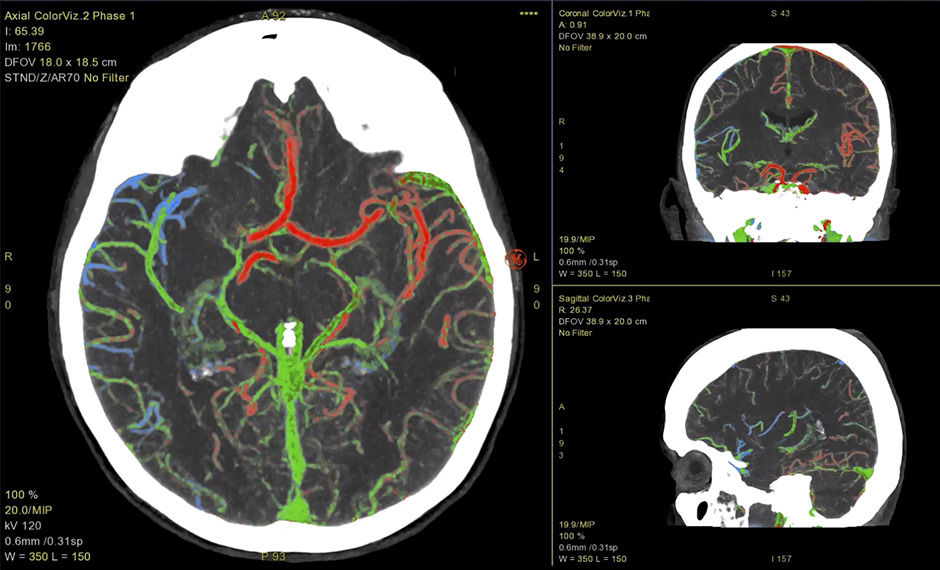

ColorViz

Zeigt eine hochentwickelte fusionierte Ansicht mit Farbdarstellung an, um die Beurteilung des Zeitpunkts der vaskulären Verstärkung zu erleichtern.